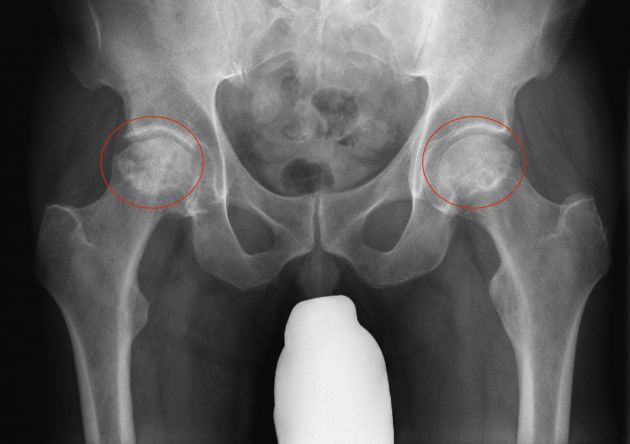

- Zunächst konventionelles Röntgen zum Ausschluss eines Einbruches der Gelenkfläche

Radiologisches Bild einer Hüftkopfnekrose beidseits mit Entrundung und Verdichtung des Hüftkopfes